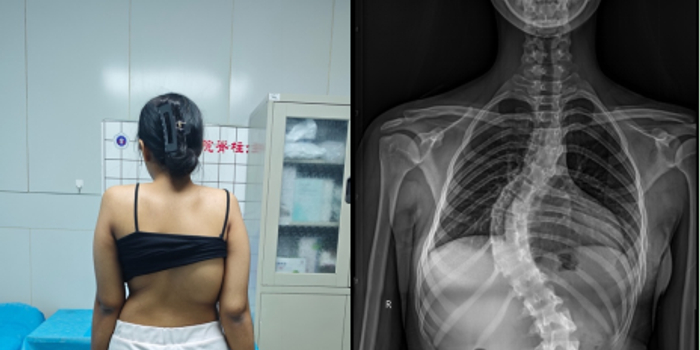

手术由脊柱与骨肿瘤病区副主任蔡璇教授主刀,李宇欢、王杰主治医师及刘璇规培医师协助,在全麻下实施后路多节段截骨矫形、植骨融合及内固定术。手术过程中需在大幅度矫正畸形的同时,严格防控脊髓神经损伤风险。神经电生理监测团队黄亚娟、孙丽君医师全程实时监测神经传导功能,为手术安全提供关键保障。在麻醉医师李路盼和手术室彭维、张宇坤主管护师的熟练配合下,历时6小时,手术顺利完成,术中出血量约600 ml,未发生神经损伤等严重并发症。术后影像学评估显示,胸椎主弯矫形率超过90%,脊柱整体序列显著改善。术后,患者在多学科团队的协同管理下恢复良好,双下肢感觉及运动功能正常,身高增加7 cm 以上。护理团队结合外籍患者需求,提供细致的围术期护理与康复指导,帮助患者顺利过渡至日常生活与学习状态。出院前,患者用英语向医护人员表达感谢:“Thank you for giving me a new life。”这不仅是对治疗效果的肯定,也体现了患者及家属对中国医疗技术与服务体系的高度认可。